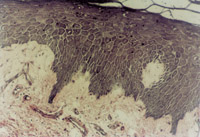

傷后12h急診入院,檢查雙下肢為淺Ⅲ度燒傷。創(chuàng)面表皮已壞死剝脫,真皮層變性壞死呈蠟黃色和蠟白色相間(圖5-3-1)。取局部組織做病理切片檢查,顯示上皮組織全層壞死,真皮層膠原纖維變性,結(jié)構(gòu)紊亂,微循環(huán)瘀滯(圖5-3-2)。

5-3-2 上皮組織全層壞死,膠原纖維變性,微循環(huán)瘀滯 HE×20